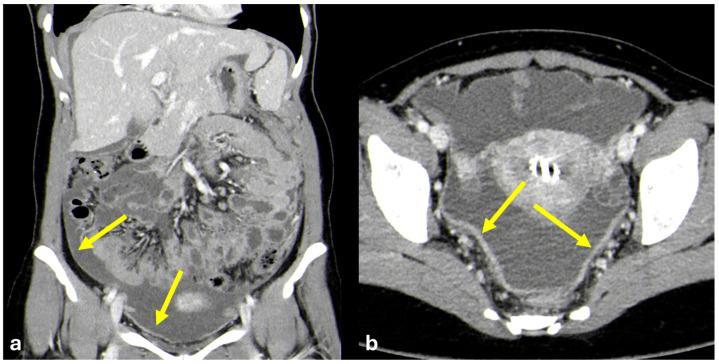

The peritoneum is a thin membrane that lines the abdominal cavity and covers the abdominal organs. It serves as a conduit for the spread of various pathological processes, including gas and fluid collections, inflammation, infections, and neoplastic conditions. Peritoneal carcinomatosis is the most common and well-known pathology involving the peritoneum, typically resulting from the dissemination of gastrointestinal and pelvic malignancies. However, numerous benign and malignant peritoneal diseases can mimic the imaging appearance of peritoneal carcinomatosis. The aim of this review is to revisit the anatomy of peritoneal compartments and elucidate the patterns of peritoneal disease spread. Emphasis is placed on identifying the distinctive imaging features of both neoplastic and non-neoplastic peritoneal diseases that differ from peritoneal carcinomatosis.

腹膜是一层薄的膜,它衬于腹腔内并覆盖腹部器官。它是各种病理过程扩散的通道,包括气体和液体聚集、炎症、感染及肿瘤性疾病。腹膜癌病是涉及腹膜的最常见且广为人知的病理情况,通常由胃肠道和盆腔恶性肿瘤的播散引起。然而,许多良性和恶性腹膜疾病可模仿腹膜癌病的影像学表现。本综述的目的是重新审视腹膜腔室的解剖结构并阐明腹膜疾病的扩散模式。重点在于识别与腹膜癌病不同的肿瘤性和非肿瘤性腹膜疾病的独特影像学特征。